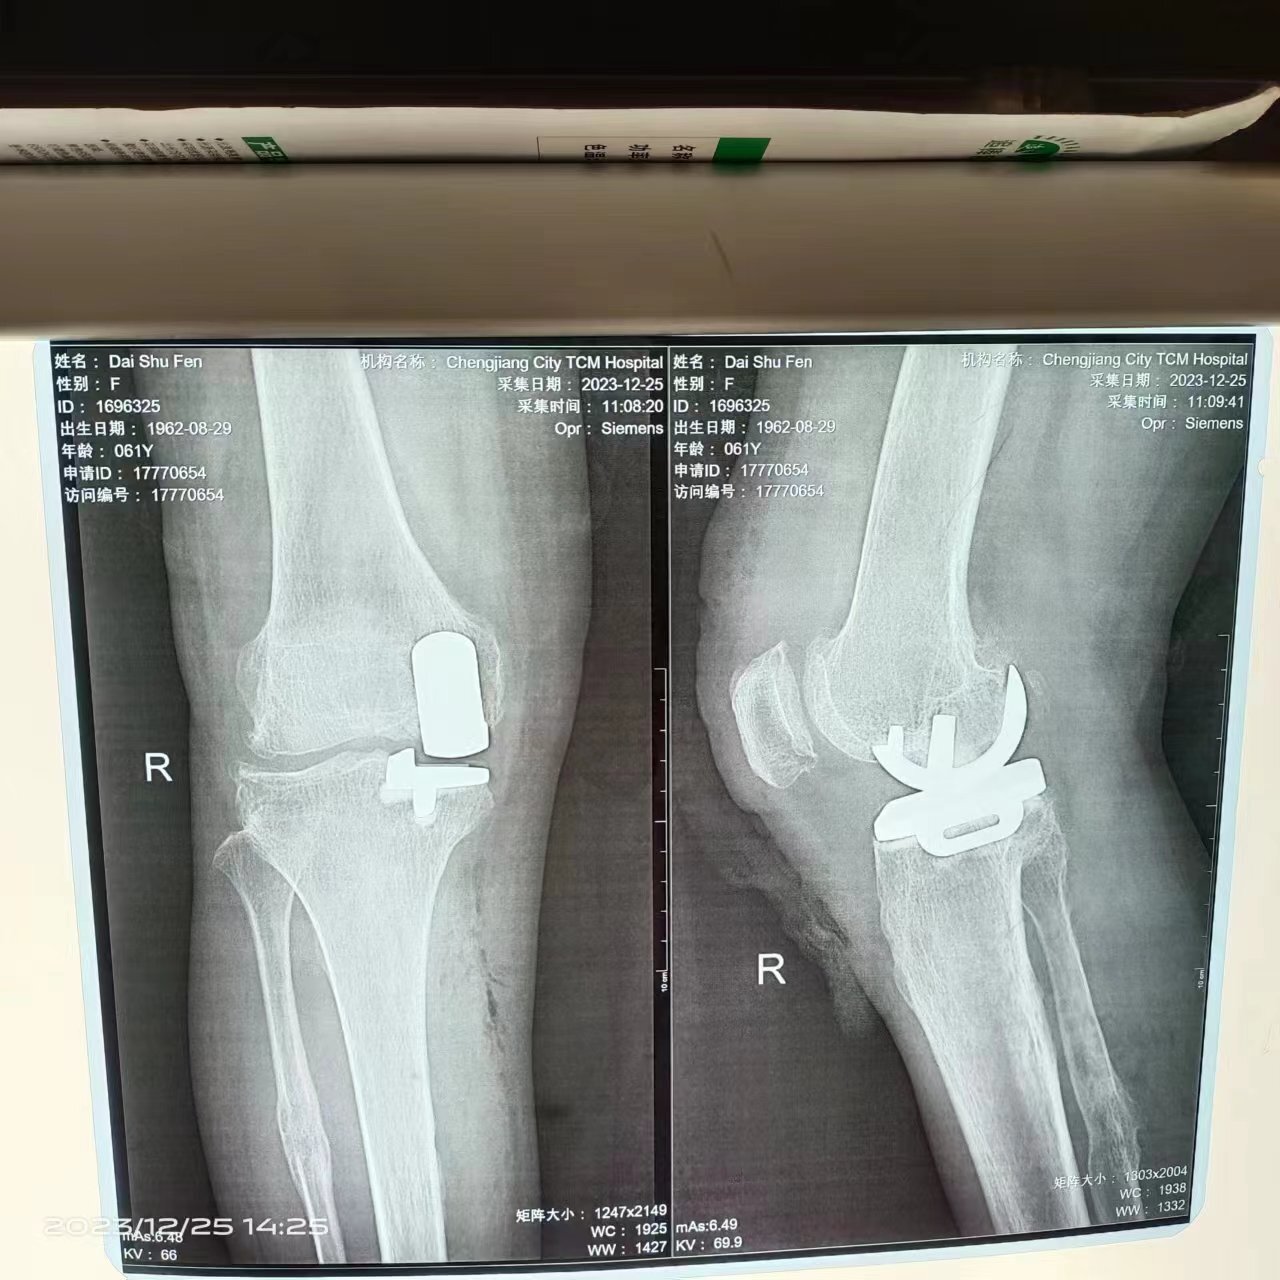

膝關(guān)節(jié)骨性關(guān)節(jié)炎保膝治療 ——單髁置換術(shù)

一個膝關(guān)節(jié)疼痛,行走加重,休息減輕。沒有打軟腿。通過休息止痛治療沒有改善?影響生活怎么辦?常規(guī)是進行人工膝關(guān)節(jié)置換術(shù),可以良好緩解疼痛。但是手術(shù)比較大,恢復(fù)慢一些。可以考慮進行部分膝關(guān)節(jié)置換術(shù),內(nèi)側(cè)單髁置換術(shù)。手術(shù)損傷小恢復(fù)快。通俗易懂的說就是膝關(guān)節(jié)內(nèi)側(cè)的半月板置換手術(shù)。

李宏鍵醫(yī)生的健康號-老李說骨2023年12月25日442